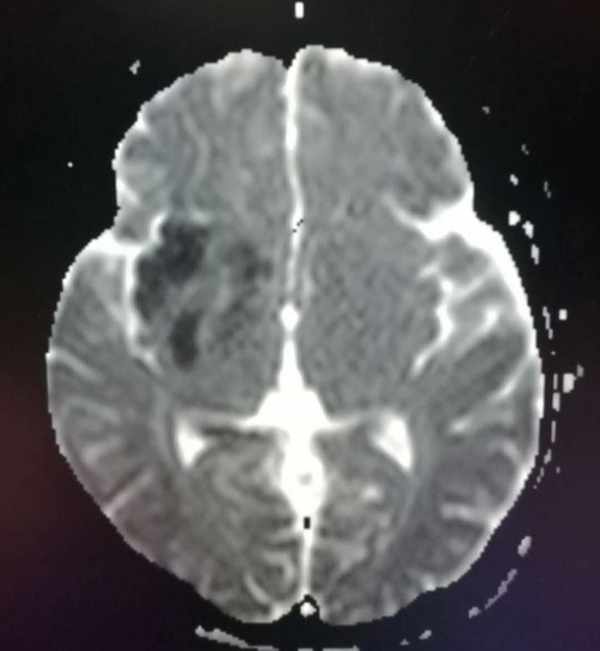

這位62歲的病人,淩晨被家人發現昏迷,急診CT發現右側大腦中動脈密度增高,呈緻密征,提示右側大腦中動脈急性腦梗死。

8小時後病情穩定下來,磁共振明確診斷,同時明確了梗死範圍: